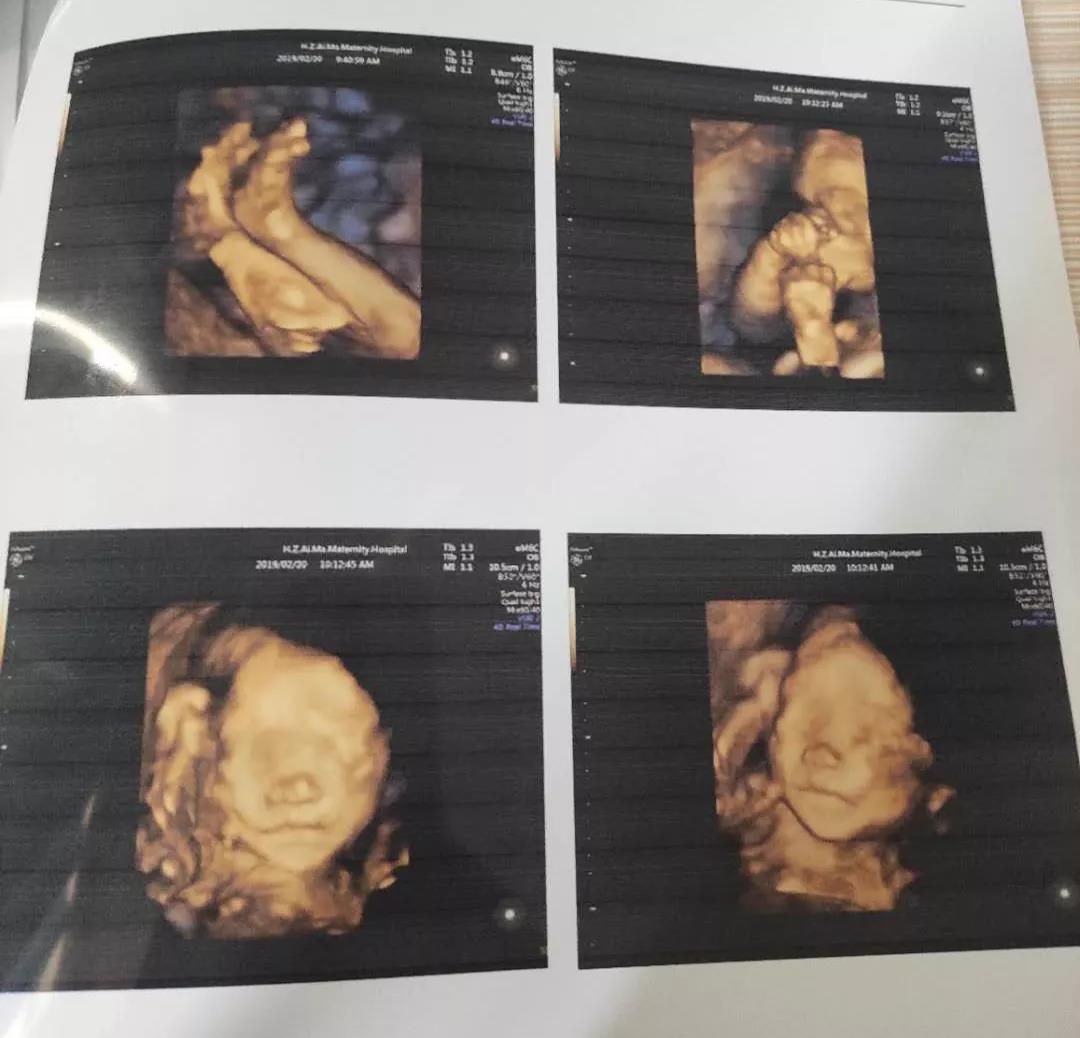

现在很多的四维彩超宣传

都集中在了给宝宝拍摄宫内写真的方面

这对于宝妈来说

当然是很有纪念意义的事情

但是事实上

四维彩超的真正意义在于:

它能够多方位、多角度地

观察宫内胎儿的生长发育情况